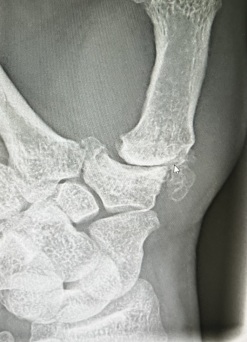

Bei Arthrosen der Gelenke kommen vielfältige operative Verfahren zum Einsatz, zum einen gelenkerhaltende Methoden - Arthroplastik oder Prothese bei Rhizarthrose - oder auch Versteifungsoperationen bei fortgeschrittenem Verschleiß der Gelenke.

Rhizarthrose / Sattelgelenksarthrose

Die Sattelgelenkarthrose beschreibt einen Knorpel-verschleiß am Gelenk zwischen dem Vieleckbein (Trapezium) und der Basis des

1. Mittelhandknochens. Die ersten Anzeichen treten häufig in Form von Belastungsschmerzen auf, wie z..B. bei alltäglichen Tätigkeiten (Flaschenöffnen, Gläser aufschrauben, Knöpfe öffnen usw.) auf. Zunächst wird konservativ behandelt mit Ruhigstellung einer Orthese, Analgetikatherapie, Spritzen mit Hyaloron oder Eigenblutkomponenten (Plasma, ACP, PRP). Bei Versagen der konservativen Therapie wird die chirurigsche Behandlung empfohlen mit Entfernung des Trapeziums und Bandplastik oder Daumensattelgelenksprothese. Der Eingriff erfolgt in Narkose oder Plexusanästhesie. Nach OP erfolgt eine Ruhigstellung bis ca. 3 Wochen, ggf. Physiotherapie. Wenn eine Prothese eingesetzt wird erfolgt die Ruhigstellung nur wenige Tage. Alltägliche kraftfordernde Tätigkeiten sind in der Regel ab dem 2. Monat nach OP wieder möglich.